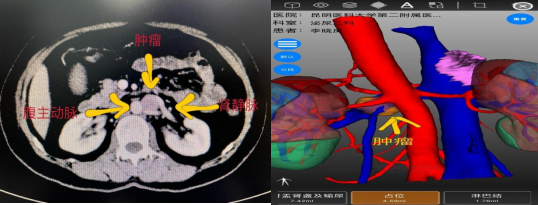

该患者既往行左肾上腺解剖性切除术,本次体检发现左侧腹膜后占位性病变,发现后患者在家人的陪伴下慕名前来财神捕鱼玩法攻略与赚钱技巧指南 | 财神捕鱼游戏网 泌尿外科二病区杨德林教授门诊就诊。患者入院后,杨德林主任团队对其病情进行详细研判后发现,该占位性病变位置非常特殊,位于腹主动脉、左肾静脉、左肾动脉之间,与左肾静脉关系尤为密切,肿瘤位置较深,周围血管关系复杂,手术难度极大,术中稍不注意就可能导致周围血管的损伤从而影响重要器官的功能。若从肿瘤位置观察经腹膜后可能相对更好显露,但患者既往有手术病史,经腹膜后途径可能粘连严重。因此,经过综合考量后,团队决定积极做术前准备,手术采用机器人辅助下经腹入路。

术前影像学检查

在狭窄的空间面对极其脆弱的人体器官,既要保证不损伤血管,又要将肿瘤完整切除,对医生手术时牵拉的力度及精细操作程度都要求极高,这也极大地增加了本次手术的难度。